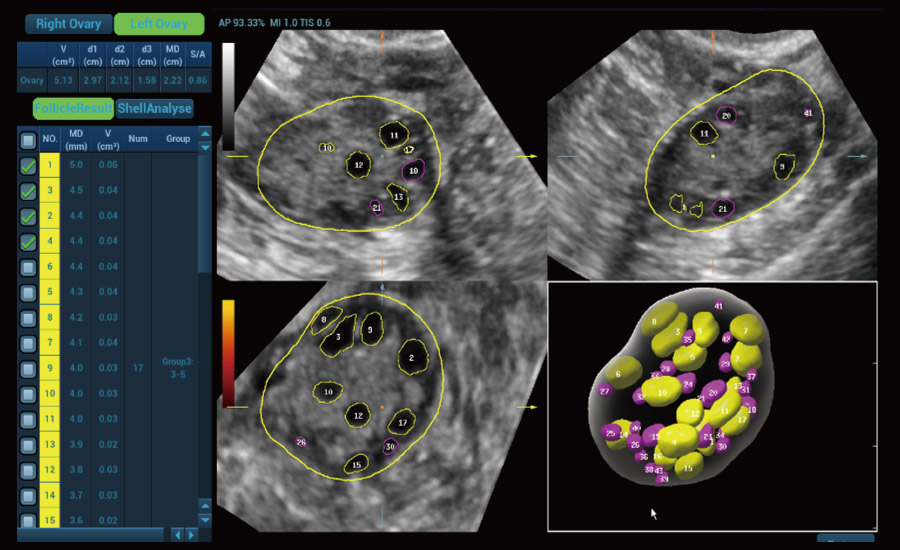

UMA (Ultra-Micro Angiography)

The innovative technology breaks the bottlenecks of traditional Doppler imaging. With ultra-high spatial resolution and flow sensitivity, it allows detecting super-subtle and super-slow flow perfusions, thereby extending the clinical application of qualitative and quantitative ultrasound evaluation in fetal brain, kidney, placenta, endometrium, ovary, etc.

Scenario-oriented Full-stack Intelligence

Combining advanced algorithms and domain-specific knowledge, the innovative Smart Scene solution enables auto identification of tissue characteristics and provides organ-specific diagnosis with full-stack intelligence. Based on auto scenario identification, the solution not only realizes smart 2D scanning with auto settings and measurements, but also delivers 3D full-stack intelligence in every step from volume imaging optimization to the difficult 2D plane acquisition, and quantification throughout whole procedure. It helps a lot in reducing the dependency on clinical skills, while increasing diagnostic accuracy, confidence and efficiency.

Fertility